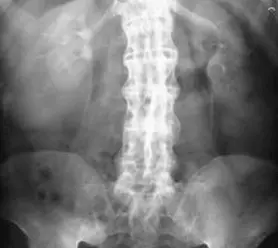

- Досить показовим є рентген при хворобі Бехтерєва.